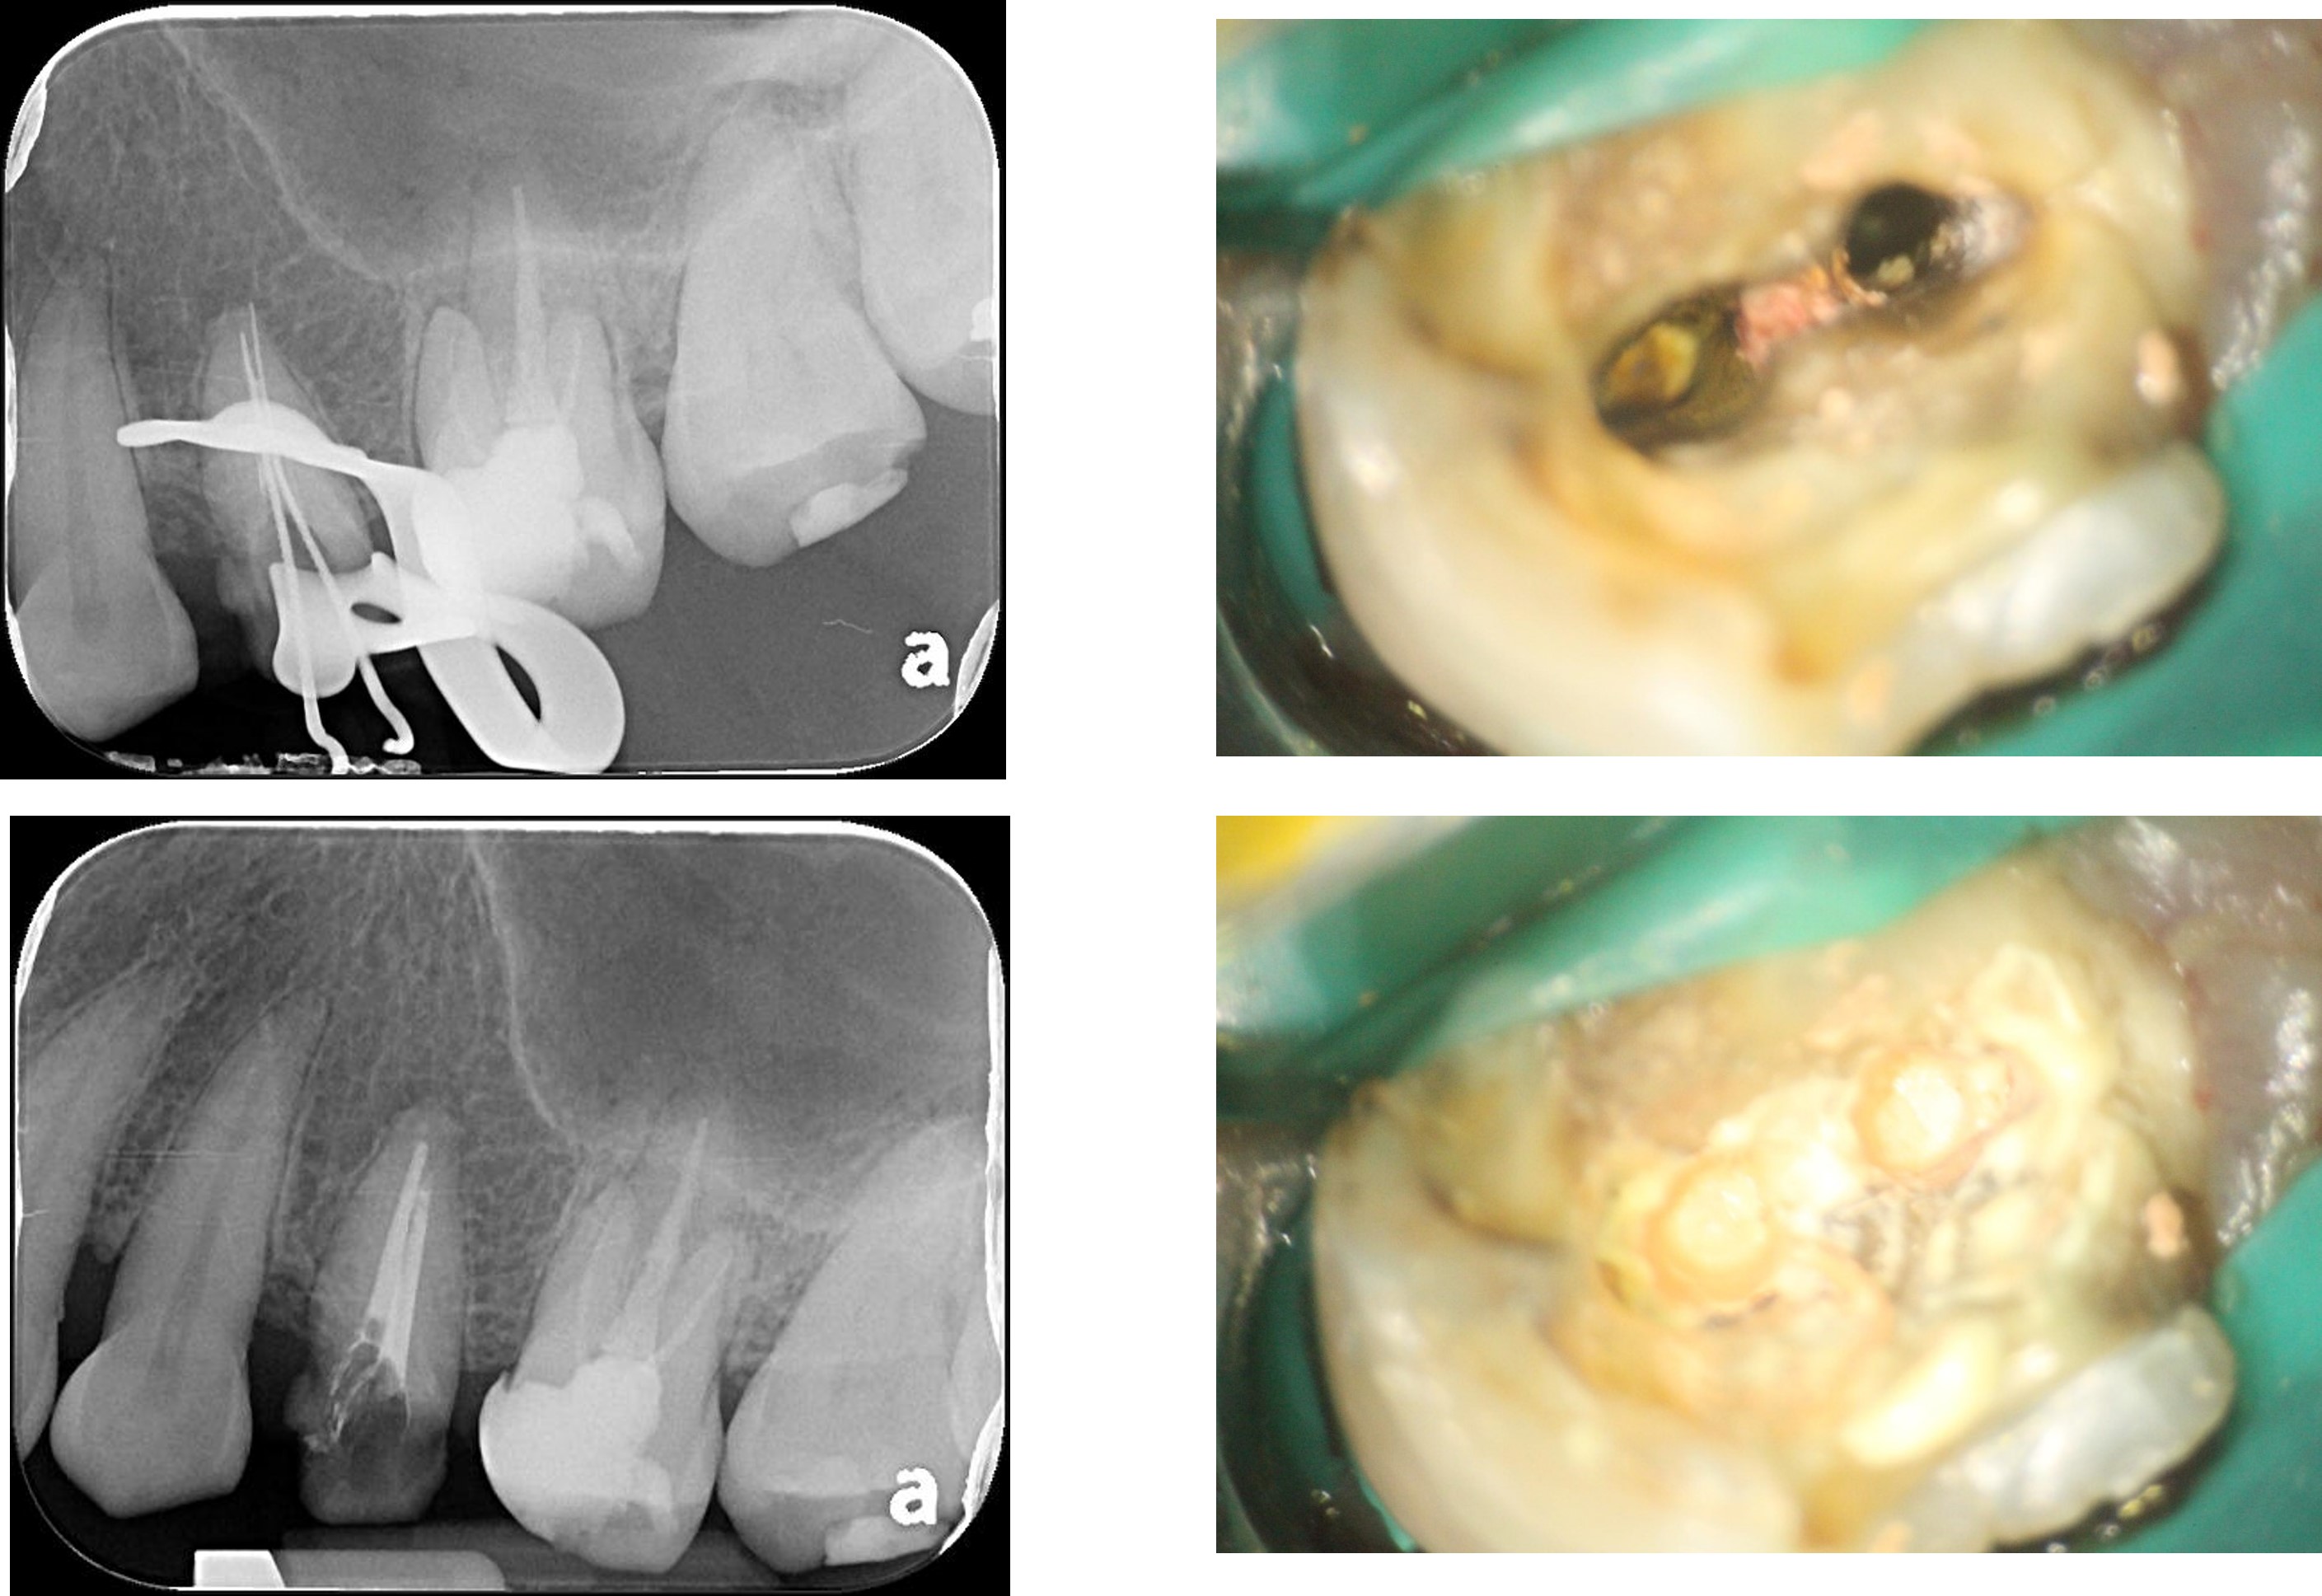

顯微根管重治療

水雷射牙冠增長手術

鑄造金屬釘柱

膺復前評估牙齦、牙齒狀態